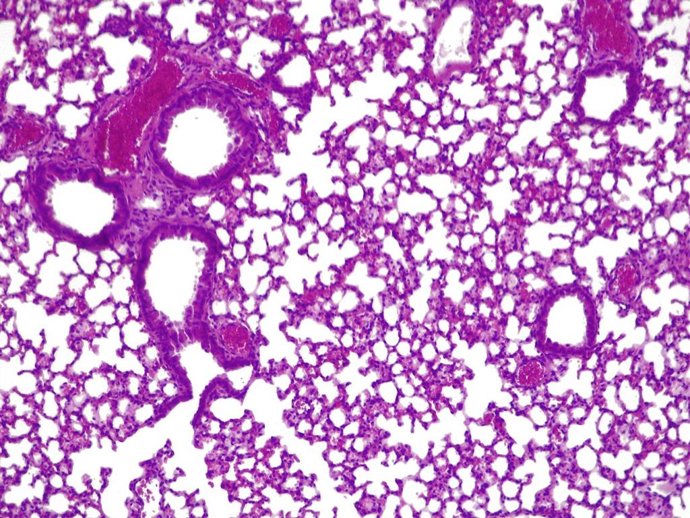

Pulmones de ratón con 'pildora viva' activa combatiendo 'presudomonas aerugionosa'

Pulmones de ratón con 'pildora viva' activa combatiendo 'presudomonas aerugionosa' - CGR/PULMOBIOTICS

La 'píldora viva' duplicó la tasa de supervivencia del ratón en comparación con la opción de no usar ningún tratamiento, y la administración de una única dosis alta no mostró signos de toxicidad en los pulmones.

Una vez que el tratamiento hubo terminado su curso, el sistema inmune innato eliminó las bacterias modificadas en un periodo de cuatro días.